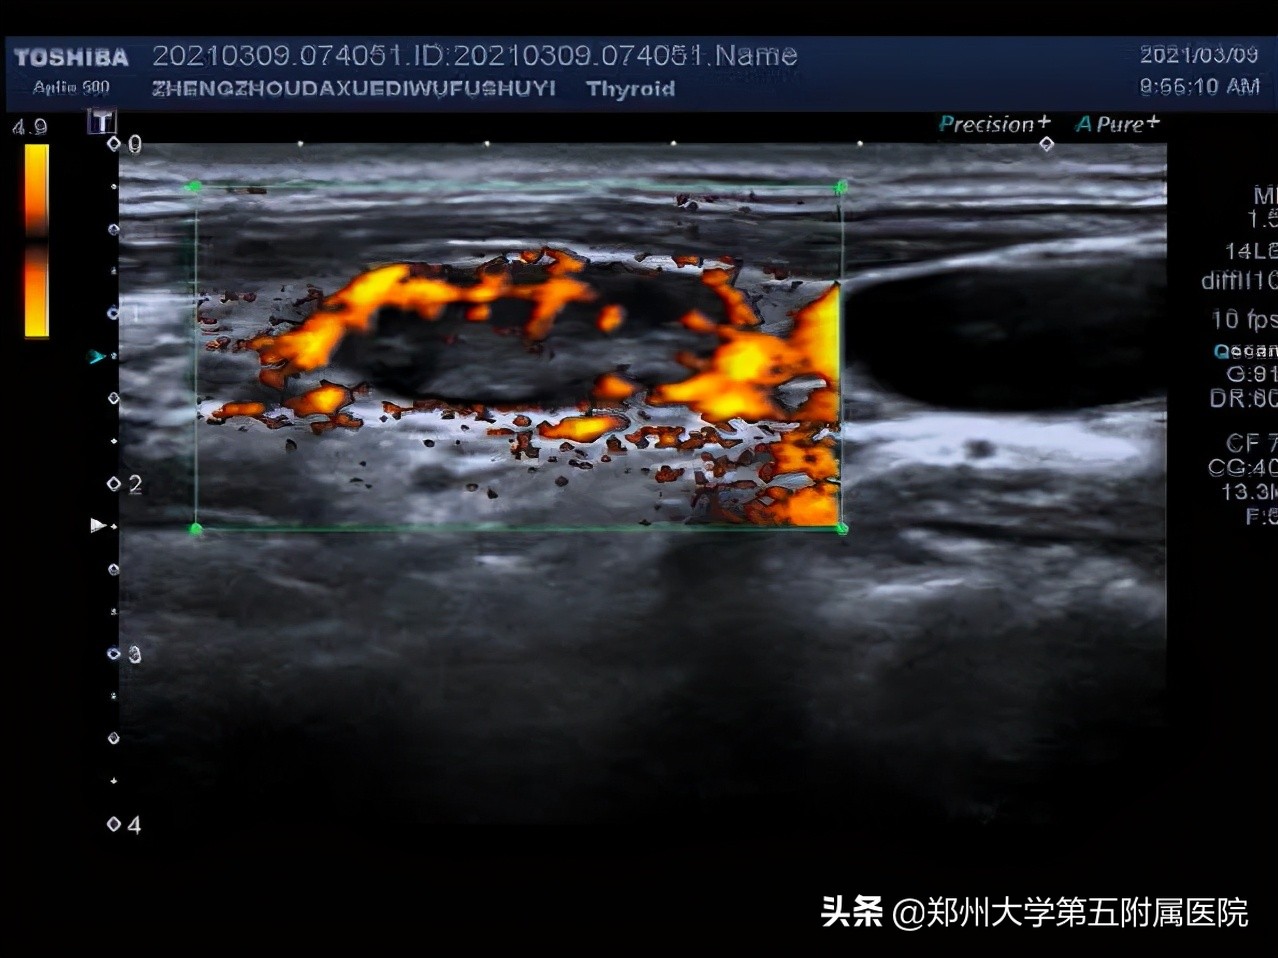

从彩超上看这个淋巴结的很多征象都提示它是恶性的,鼻咽癌比较隐匿,多例鼻咽癌就是这样发现的。

1.淋巴结皮髓质分界不清

2.淋巴结内部有液化

3.淋巴结血流为周边型,没有淋巴门。